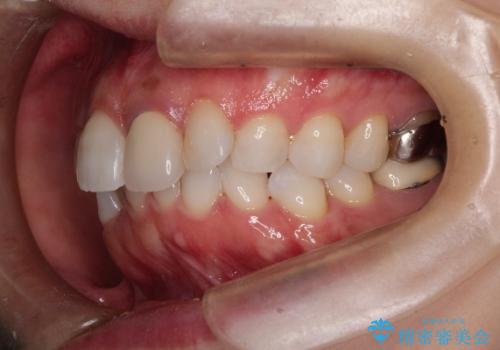

インビザラインによる非抜歯矯正 ガタガタな歯並びを整った歯並びへ

- 上下の全体的ながたつきが気になるとのことで来院されました。

マウスピースでの目立たない矯正を希望されたので、インビザラインでの治療となりました。

全体的に歯と歯の間にわずかに隙間を作り、歯を並べました。